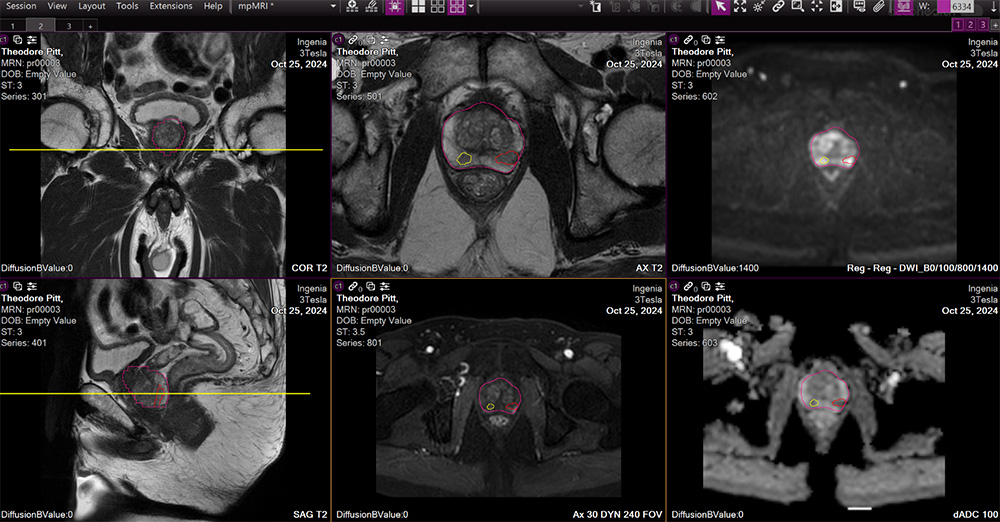

An AI-powered suite of modular applications that streamline prostate MRI interpretation, analysis, and biopsy planning workflows. The solution integrates automated lesion detection and risk classification, intelligent gland segmentation with PSA density calculation, and PI-RADS-compliant reporting into a single platform.

Aids detection and characterization of suspicious prostate cancer lesions on MRI with automated ROI candidate identification and per-lesion risk classification at high sensitivity.

Automatically contours the prostate gland and lesion ROI candidates, providing precise volume measurements while allowing manual refinement when needed.

Supports consistent lesion evaluation and biopsy recommendations for PI-RADS assessment with key findings and sector maps automatically pre-populated in structured reporting.